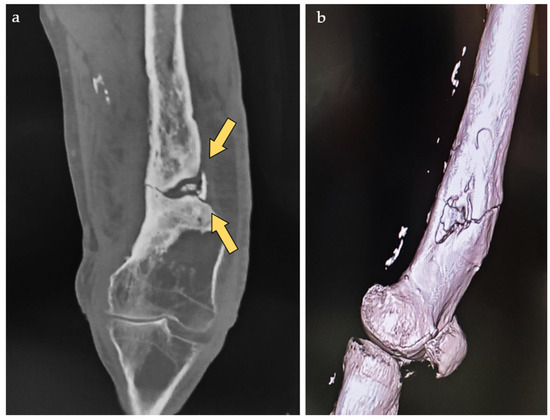

The management of severely comminuted acetabular posterior wall fractures in young, active patients presents a significant surgical challenge. When anatomical open reduction and internal fixation (ORIF) is not feasible, primary total hip arthroplasty (THA) is often considered but is a suboptimal solution due to concerns over long-term implant survivorship and the inevitability of revision surgery. This single-patient technical note presents a novel joint-preserving technique for managing unreconstructible acetabular posterior wall fractures using with cement-augmented screw fixation via the Kocher–Langenbeck approach. A 28-year-old male sustained a left posterior hip dislocation with a comminuted acetabular posterior wall fracture involving >30% of the articular surface, alongside a tibial shaft fracture, following a high-energy motorcycle collision. Intraoperative assessment confirmed the posterior wall was unreconstructible, with six non-viable osteochondral fragments. A joint-preserving salvage procedure was performed. After debridement, a stable metallic framework was created using three screws anchored in the posterior column. Polymethylmethacrylate (PMMA) bone cement was then applied over this framework in its doughy phase, meticulously contoured to reconstruct the articular surface. The hip was reduced, and the tibia was fixed with an intramedullary nail. The patient was mobilized with weight-bearing as tolerated on postoperative day 3. At the 21-month follow-up, the patient reported no pain during daily activities and only mild discomfort during deep squatting. Radiographic and CT evaluations demonstrated a stable hip joint, concentric reduction, well-maintained joint space, and no evidence of implant loosening or osteolysis. Level of Evidence: V (Technical Note/single-patient Case report). For unreconstructible, comminuted fractures of the non-weight-bearing portion of the acetabular posterior wall in young patients, cement-augmented screw fixation offers a viable joint-preserving alternative to primary THA. This technique provides immediate stability, facilitates early mobilization, and preserves bone stock. While long-term outcomes require further study, this case demonstrates excellent functional and radiographic results at 21 months, presenting a promising new option for managing these complex injuries. Full article

Show Figures

Figure 1